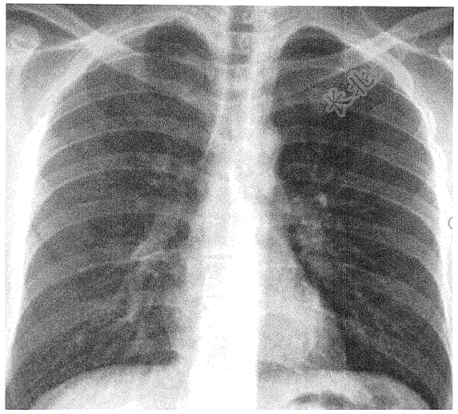

- 单项选择题男性,26岁,胸痛1小时( )

A、右侧气胸

B、左肺炎症

C、左侧液气胸

D、右侧肺炎

E、左侧气胸